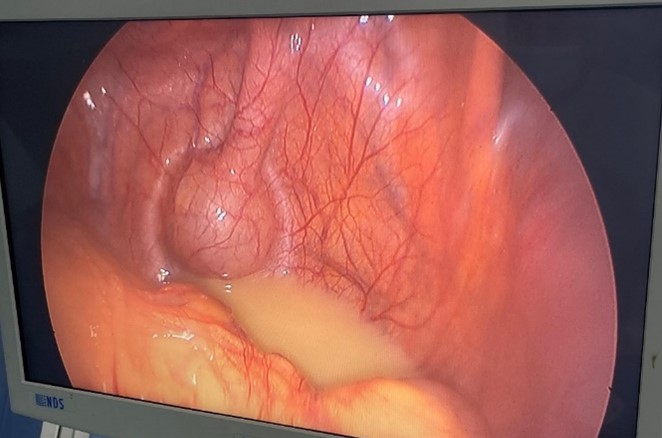

The patient was admitted urgently to the operating room after appropriate preoperative management. A laparoscopic approach was initially chosen. Initial exploration revealed a small amount of purulent peritoneal effusion and a left paraduodenal hernia. Reduction of the hernia contents was not feasible laparoscopically due to dense intrasaccular adhesions. Consequently, conversion to a midline laparotomy was performed.

Figure 2: Purulent peritoneal effusion observed during laparoscopic exploration.